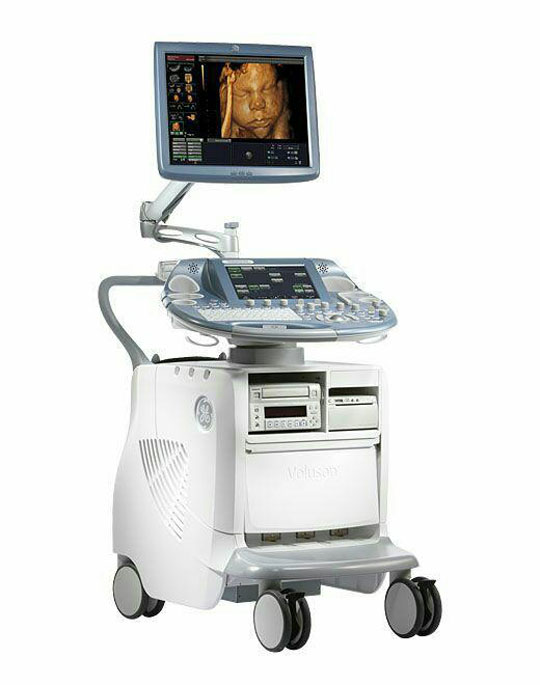

کاربرد و انواع سونوگرافی

کاربرد و انواع سونوگرافیسونوگرافی یا تصویربرداری اولتراسوند، روش تصویربرداری ایمن و بدون درد از اندام های بدن است. و از امواج صوتی استفاده میشود که برای بدن ضرری ندارد . ...

مركز سونوگرافى و راديولوژى شقايق واقع در يوسف آباد تهران با بهره گيرى از عوامل فوق الذكر تلاش كرده است تا در ارائه بهترين خدمات راديولوژى و همچنين بهترين سونوگرافى دقيق در يوسف آباد تهران كه در ذيل فهرست وار آمده است در خدمت عزيزان هموطن درتهران و سرتاسر ايران باشد.

رادیولوژی و سونوگرافی شقایق تهران یکی از مراکز تخصصی است که با تجهیزات مدرن و به روز میتواند انواع خدمات تشخیصی درمانی در این زمینه را به مراجعین ارائه نماید. آدرس مطب : منطقه شش ٦ - تهران ، یوسف آباد ، خیابان فتحی شقاقی ، بین چهلستون و بیستون ، راديولوژي و سونوگرافى شقايق، دكتر سيف